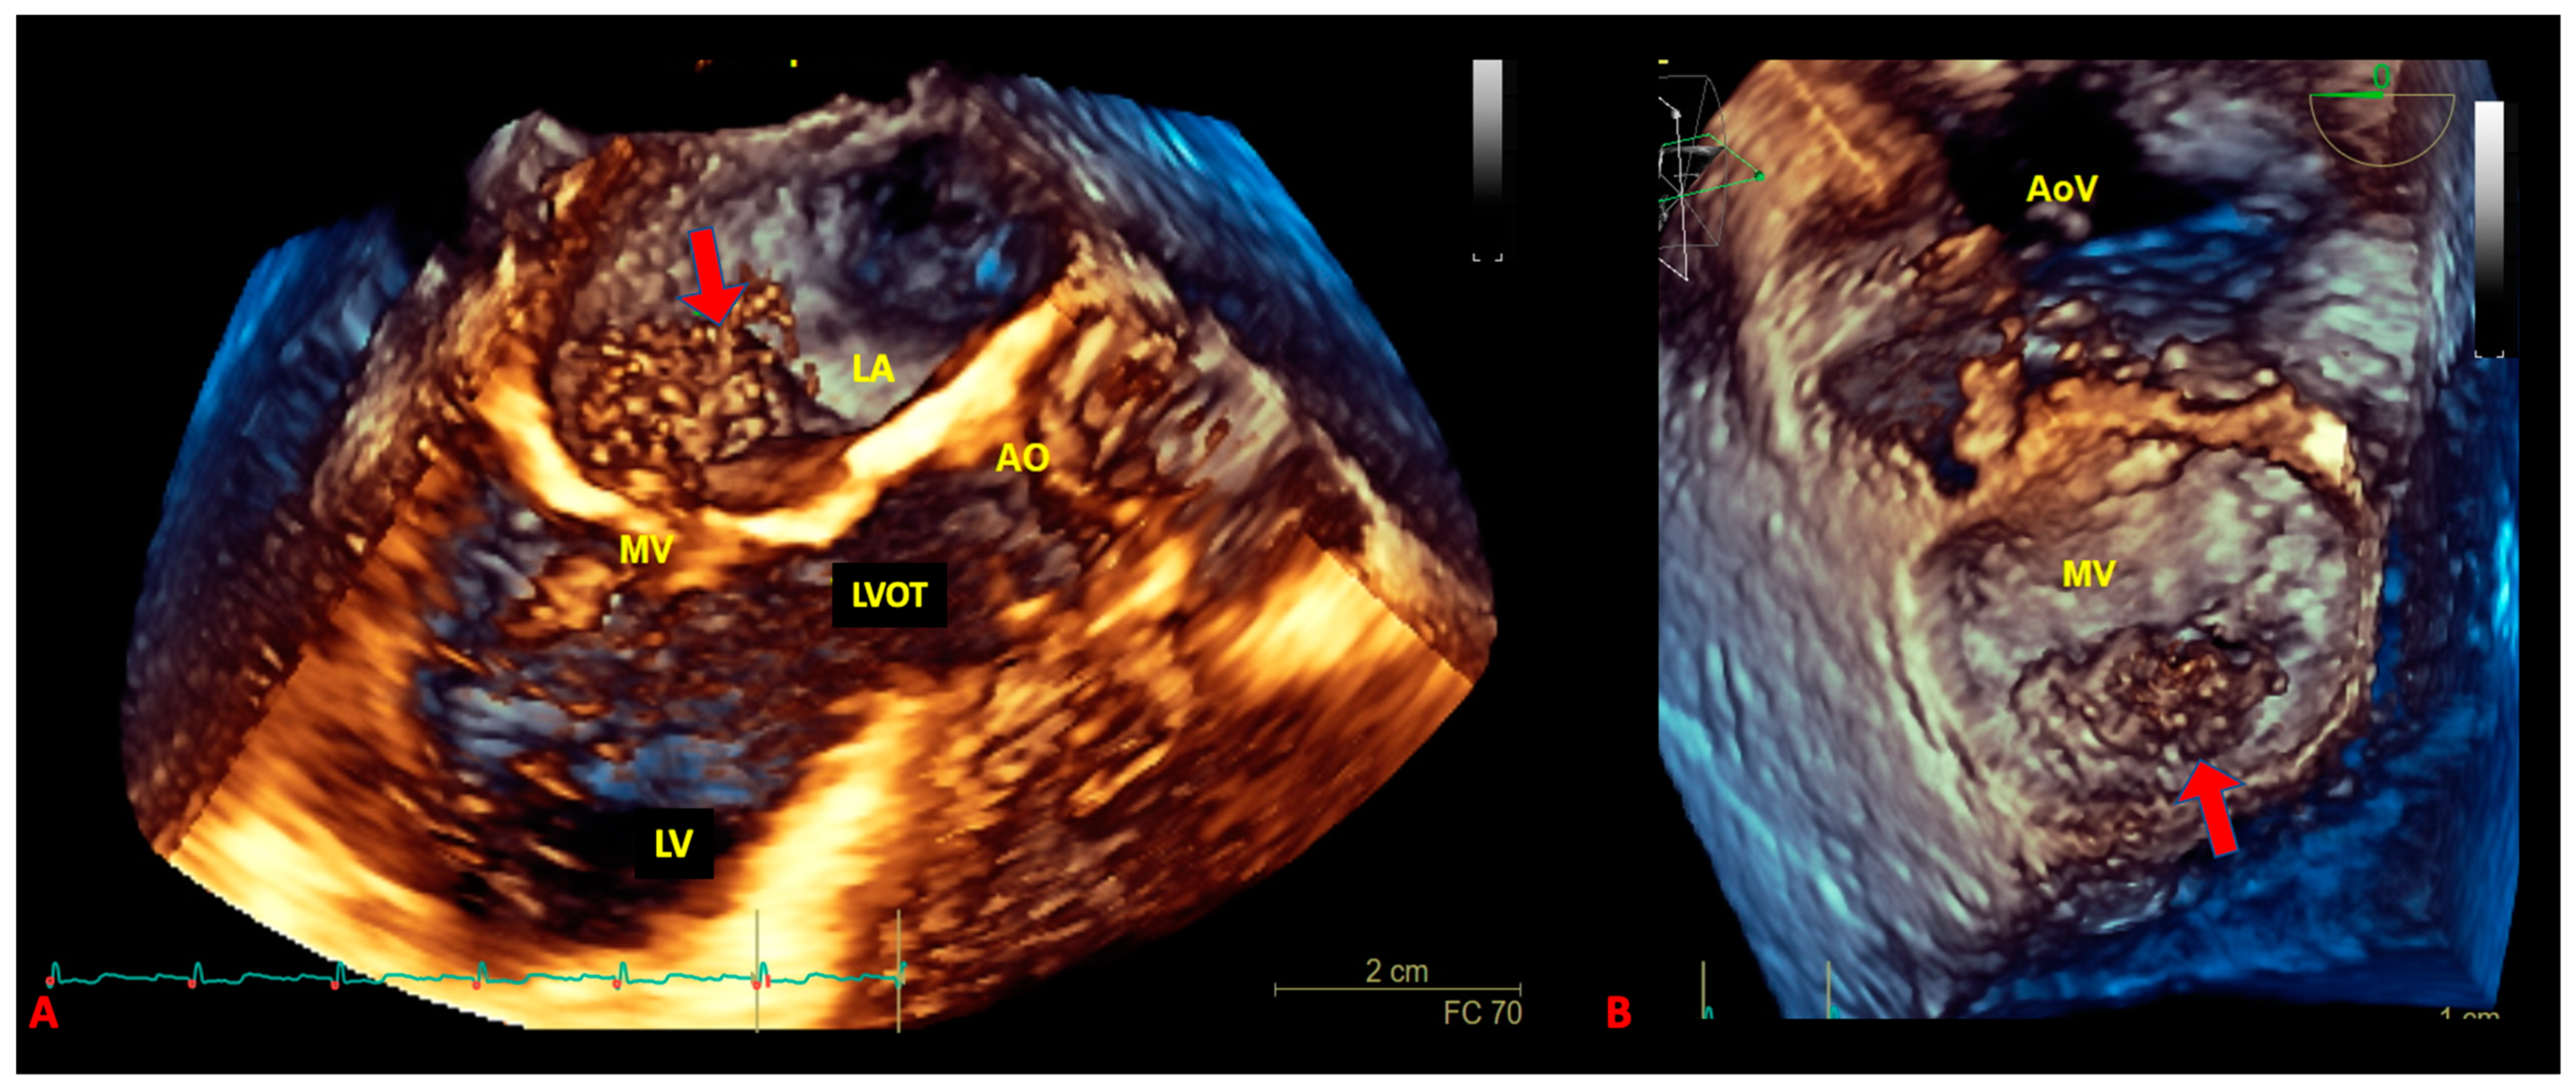

3. The Role of Echocardiography in pSTS-h

- Mankad, R.; Herrmann, J. Cardiac tumors: Echo assessment. Echo Res. Pract. 2016, 3, R65–R77. [Google Scholar] [CrossRef] [PubMed]

- Kohsaka, S.; Ara, V.; Feghali, S.F.; Stainback, R. Harmonic contrast transesophageal echocardiography of a soft-parts sarcoma metastatic to the heart. Tex. Hear. Inst. J. 2005, 32, 610–611. [Google Scholar]

- Lang, R.M.; Mor-Avi, V. Clinical utility of contrast-enhanced echocardiography. Clin. Cardiol. 2006, 29, I15–I25. [Google Scholar] [CrossRef]

- Kirkpatrick, J.N.; Wong, T.; Bednarz, J.E.; Spencer, K.T.; Sugeng, L.; Ward, R.; DeCara, J.M.; Weinert, L.; Krausz, T.; Lang, R.M. Differential diagnosis of cardiac masses using contrast echocardiographic perfusion imaging. J. Am. Coll. Cardiol. 2004, 43, 1412–1419. [Google Scholar] [CrossRef]

- Guta, A.C.; Badano, L.P.; Ochoa-Jimenez, R.C.; Genovese, D.; Previtero, M.; Civera, S.; Ruocco, A.; Bettella, N.; Parati, G.; Muraru, D. Three-dimensional echocardiography to assess left ventricular geometry and function. Expert Rev. Cardiovasc. Ther. 2019, 17, 801–815. [Google Scholar] [CrossRef] [PubMed]

- Asch, F.M.; Bieganski, S.P.; Panza, J.A.; Weissman, N.J. Real-Time 3-Dimensional Echocardiography Evaluation of Intracardiac Masses. Echocardiography 2006, 23, 218–224. [Google Scholar] [CrossRef]

- Gok, G.; Elsayed, M.; Thind, M.; Uygur, B.; Abtahi, F.; Chahwala, J.R.; Yıldırımtürk, Ö.; Kayacıoğlu, İ.; Pehlivanoğlu, S.; Nanda, N.C. Incremental value of live/real time three-dimensional transesophageal echocardiography over the two-dimensional technique in the assessment of primary cardiac malignant fibrous histiocytoma. Echocardiography 2015, 32, 1164–1170. [Google Scholar] [CrossRef]